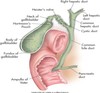

anatomy of gallbladder image

GB & biliary sysem

normal relational anatomy image

GB anatomy image